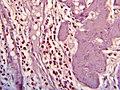

Histopathology

Histopathology is indicated if preoperative imaging and/or gross examination gives a suspicion of gallbladder cancer.[29]